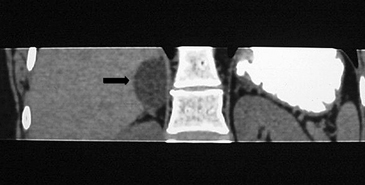

Los sitios más habituales de metástasis son hígado, pulmón, además de la invasión de las estructuras vasculares adyacentes, especialmente de la vena cava inferior, hallazgo que constituye una consideración fundamental al momento de planificar el abordaje quirúrgico (Figura 23 a y b).

Figura 23. Carcinoma suprarrenal derecho. Corte axial de resonancia magnética ponderado en T2 con saturación grasa (a) en que se demuestra una masa suprarrenal derecha con áreas hiperintensas en su espesor probablemente determinadas por necrosis (flecha) y corte coronal en secuencia TRUFISP (b) en que se observa un trombo tumoral que expande el lumen de la vena cava inferior (cabeza de flecha).Puede también presentar invasión directa de otras estructuras vecinas, como riñón, páncreas, bazo y diafragma.